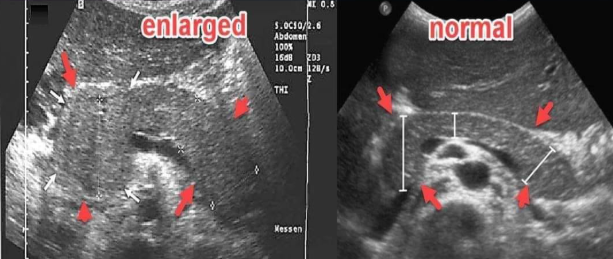

The pathology demonstrated on the left image is most likely:

Diffuse acute pancreatitis

What pathology is suggested by the findings in the image on the right? (left is normal)

Chronic pancreatitis (calcifications + heterogenous appearance)